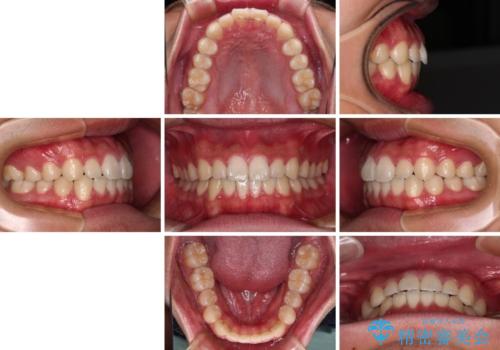

- 20代男性

- インビザライン・ライト

- 8ヶ月

- 上下前歯の叢生を気にして来院された患者様です。

費用を抑え、期間もあまりかけずに治療をしたいとのことで、インビザライン・ライトを用いて矯正治療を行うこととしました。

インビザライン・ライトは、製作できるアライナーの枚数に制限があるため、移動可能な量に限りがあります。

一方で、半年から1年程度で治療を終えることができるため、軽度の歯列不正の患者様には大変お勧めです。